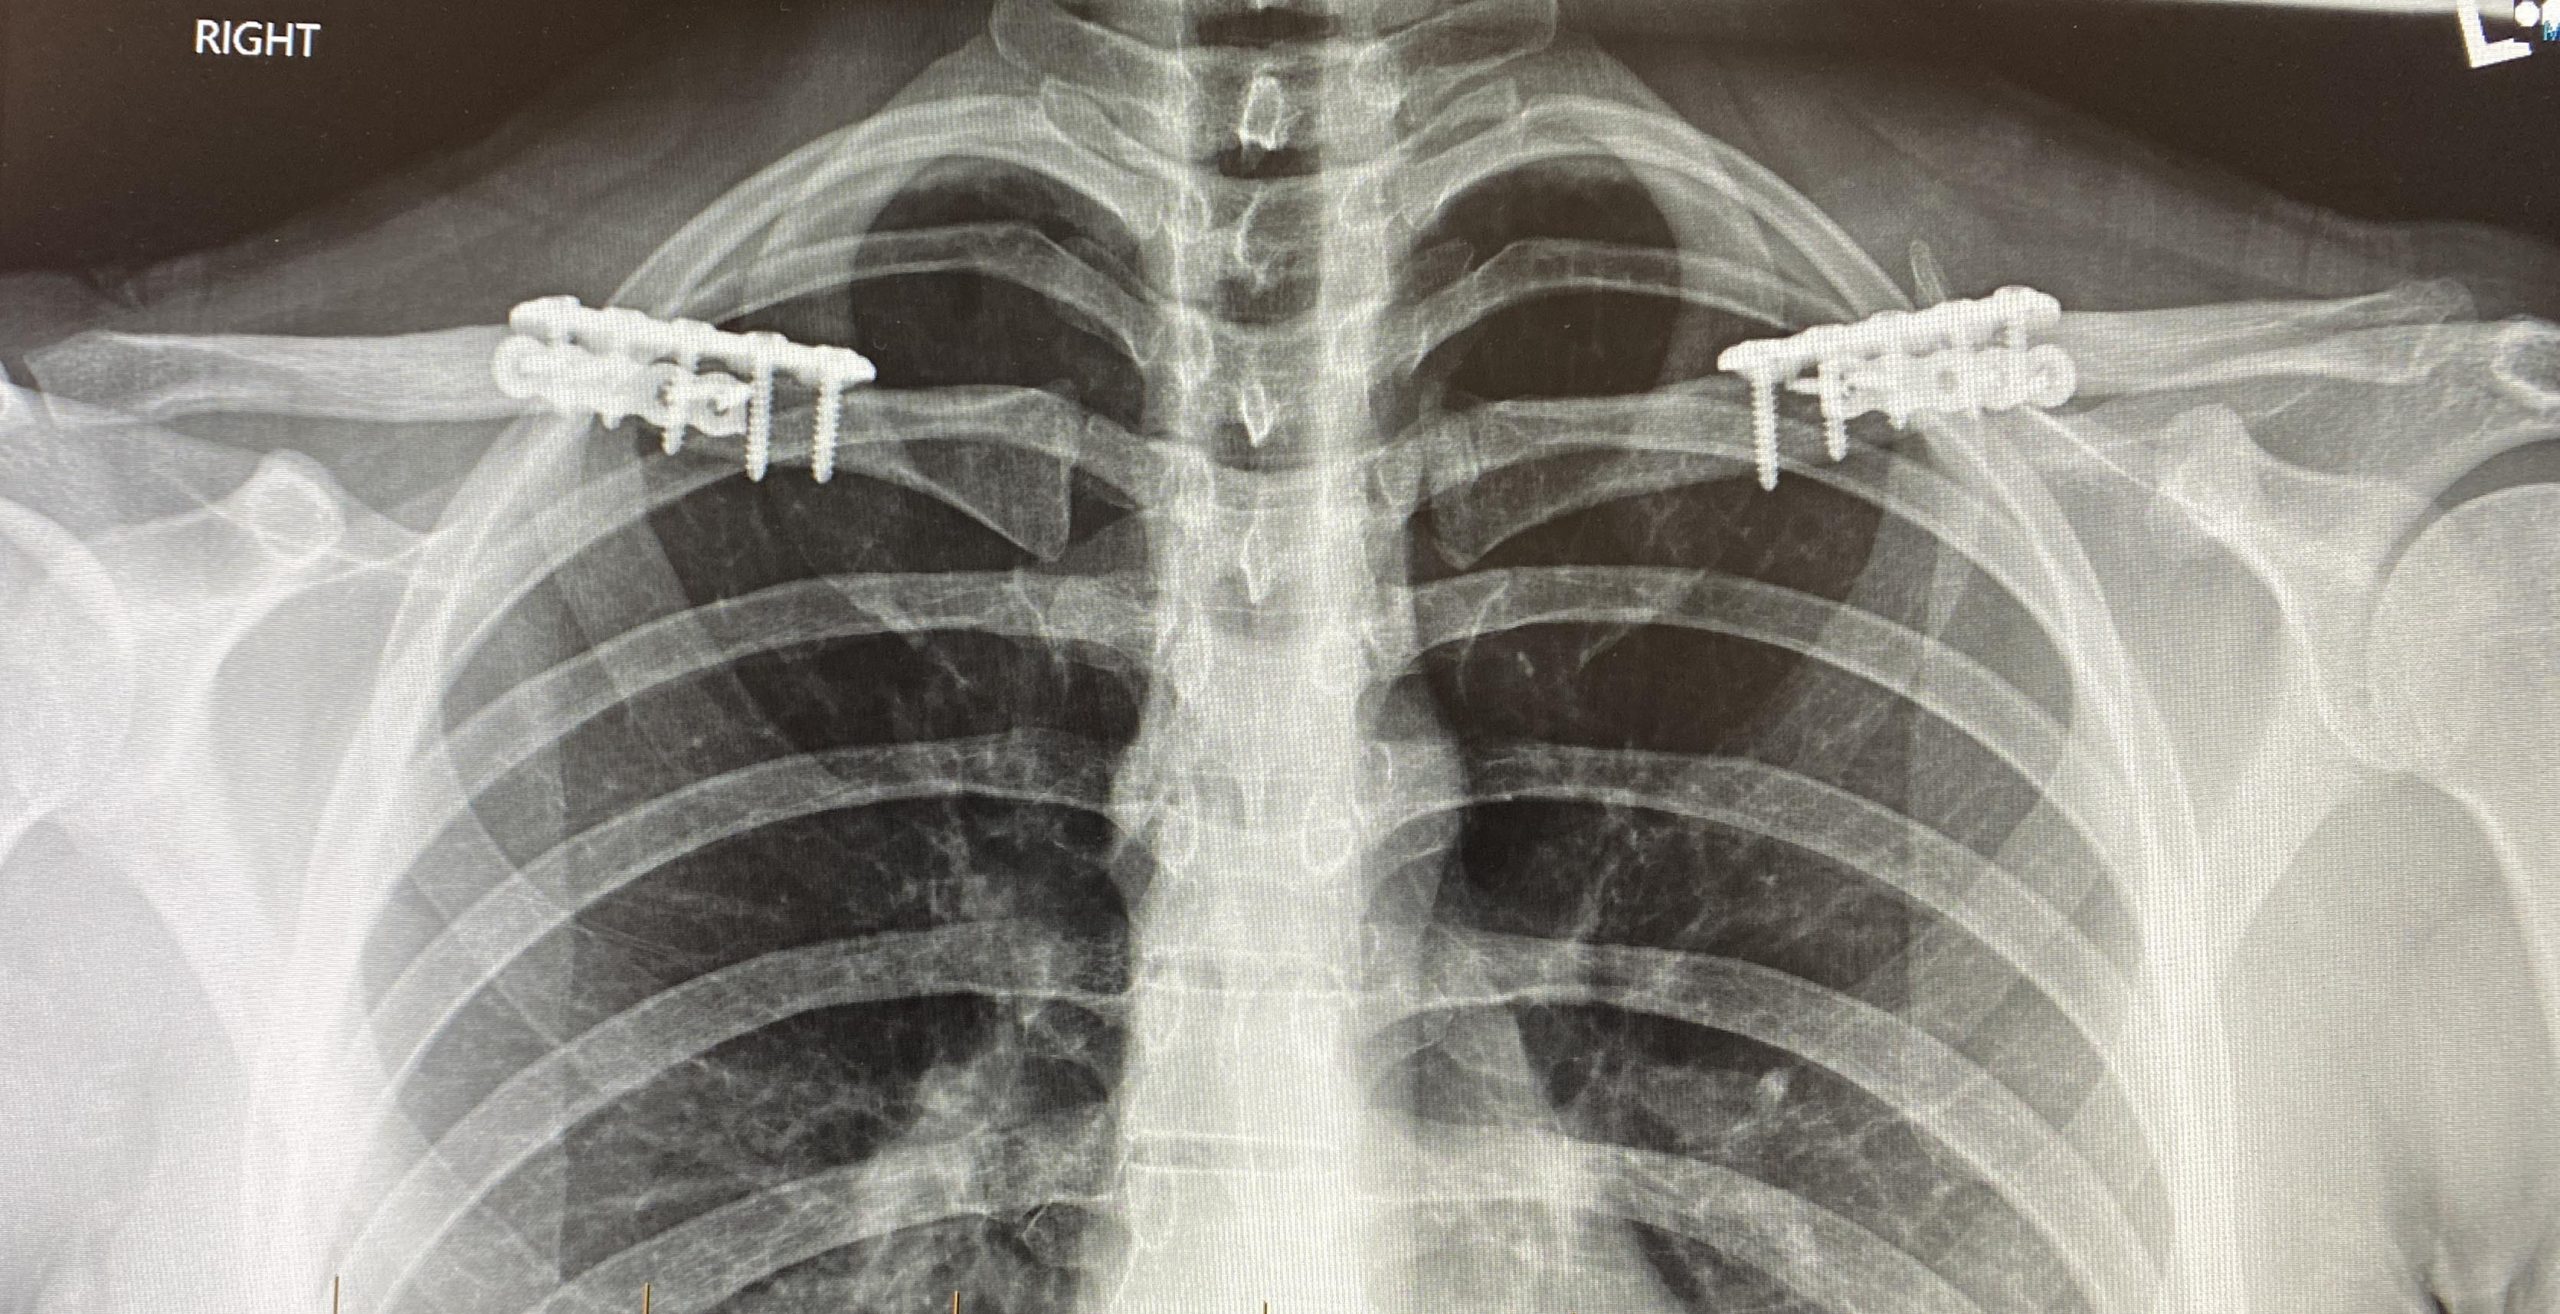

Clavicle Fracture Surgery Shoulder Surgeon Santa Barbara, Santa Shoulder Surgery Xray Shoulder arthroplasty is the primary treatment of advanced glenohumeral arthritis once conservative measures fail,. This article reviews normal and abnormal imaging findings of the shoulder after surgery for subacromial impingement, rotator cuff. A diagram of an anatomic shoulder replacement—the plastic socket replaces the cup of the scapula (shoulder blade). Massive rotator cuff injuries may require shoulder replacement surgery. Shoulder Surgery Xray.